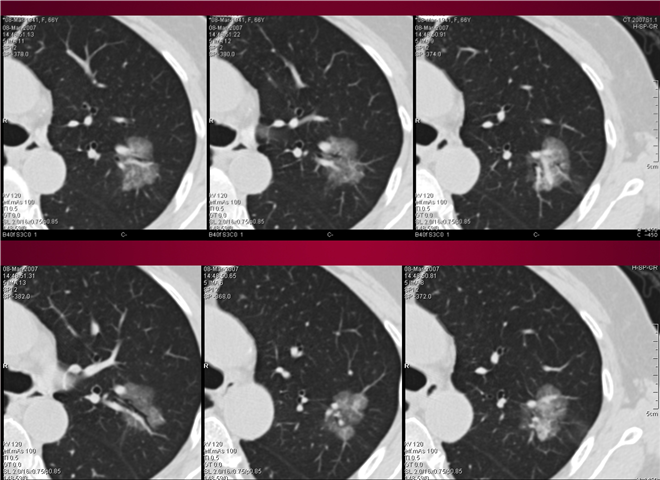

23_CT读片基础